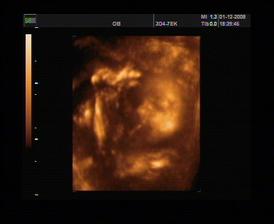

20.8.2008 druhý ultrazvuk a druhá fotečka,